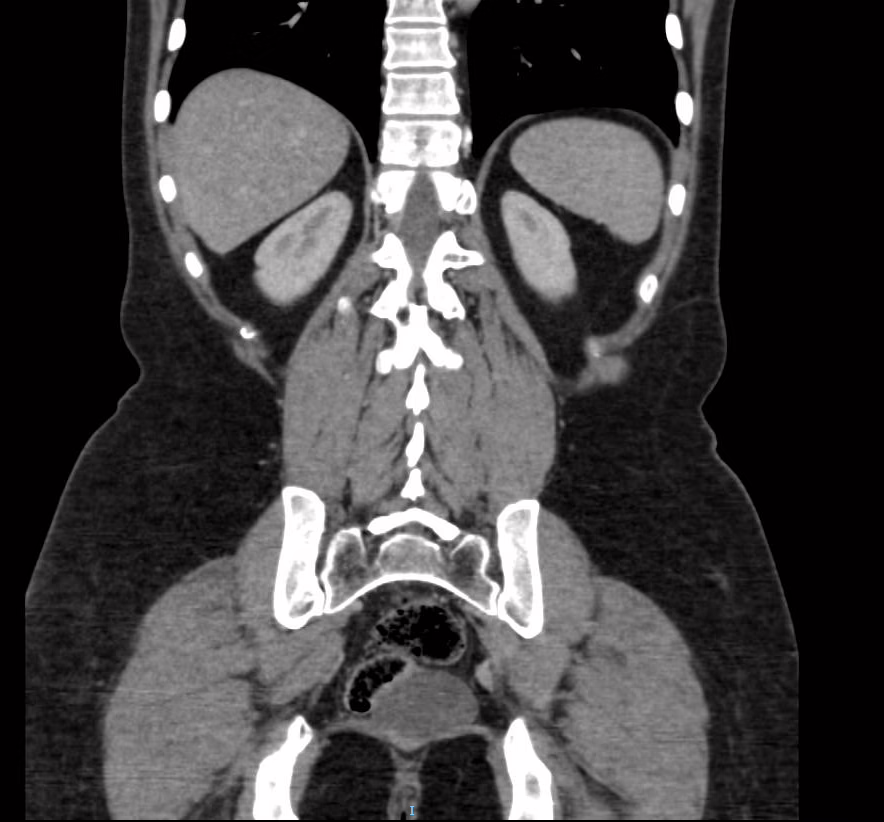

Abdomen

Hígado es de forma, tamaño (12.5) y densidad habitual, sin evidencia de aparentes lesiones parenquimatosas, sin dilatación de la vía biliar intra o extrahepática.

Colédoco con calibre de 2.9 mm.

Vena porta con calibre de 7.79 mm.

Vesícula biliar de características normales.

Páncreas de apariencia normal.

Bazo de apariencia normal (9.8 cm).

Ambos riñones se encuentran en su topografía habitual, son de forma y tamaño normal (riñón derecho en su eje longitudinal mide 10.62 cm e izquierdo 10.5 cm). No se observan lesiones sólidas ni litos o ectasia del sistema colector.

Ambas glándulas suprarrenales presentes y normales.

En espacio pre sacro posterior a ámpula rectal, con presencia de imagen redondeada, regular, bien definida, de contenido hipodenso (3 UH), tras la administración de contraste sin evidencia de realces, que mide 5.3 X5.14X 5.6 cm, en su eje longitudinal, anteroposterior y trasversal respectivamente con volumen aproximado de 80 cc.

EN EL PRESENTE ESTUDIO TOMOGRÁFICO, EXISTE COLECCIÓN EN ESPACIO PRESACRO, POSTERIOR ÁMPULA RECTAL CON DENSIDAD LÍQUIDA, QUE MIDE 5.3 X5.14X 5.6 CM, CON VOLUMEN APROXIMADO DE 80 CC, SUGERENTE DE ENDOMETRIOSIS PERITONIAL VS ORIGEN A DETERMINAR.